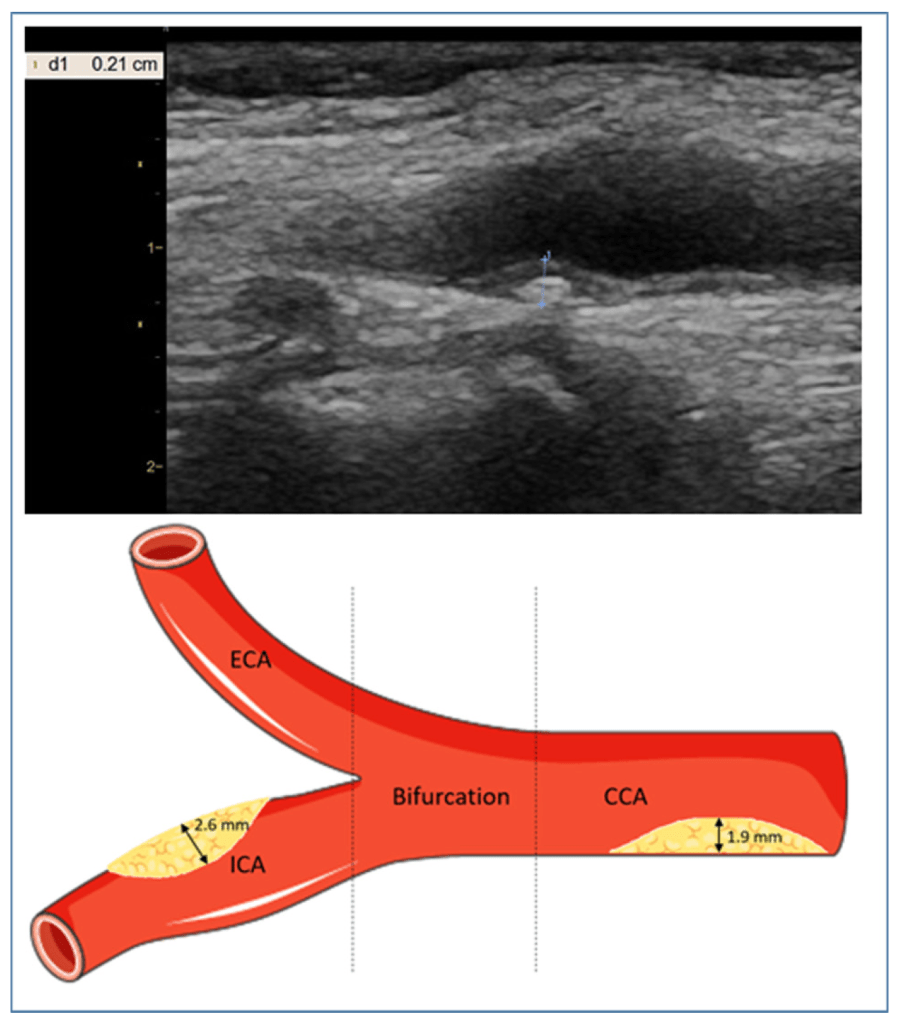

Calculation of carotid plaque score.

The primary outcome measures were US measures of carotid artery structure: cIMT, PS, PV, GSM. The secondary measures were of pulse wave velocity (PWV) at different times (BS and ES). These were measured on 3 occasions: baseline, 12 weeks (after treatment phase), and 24 weeks (12 weeks post treatment).

Plaque score (PS) is a strong predictor of ischaemic stroke and major adverse cardiovascular events (MACE – this acronym has figured on the blog previously).[2]

There were significant differences between groups in PS following the treatment phase and at the later follow-up. It is hard to interpret these, as they are expressed in millimetres change, whereas the PS is usually a numerical score based on the thickness of the thickest plaques in 4 different regions of the carotid: common portion, bifurcation, external, internal. It looks as though the biggest change was just under 0.5mm, which may not be enough to change the standard numerical score where the difference between each number is 1mm of plaque thickness. Anyway, it is the right direction, and it gets me thinking about possible mechanisms, and whether or not it is really necessary to needle close to the artery in first place.